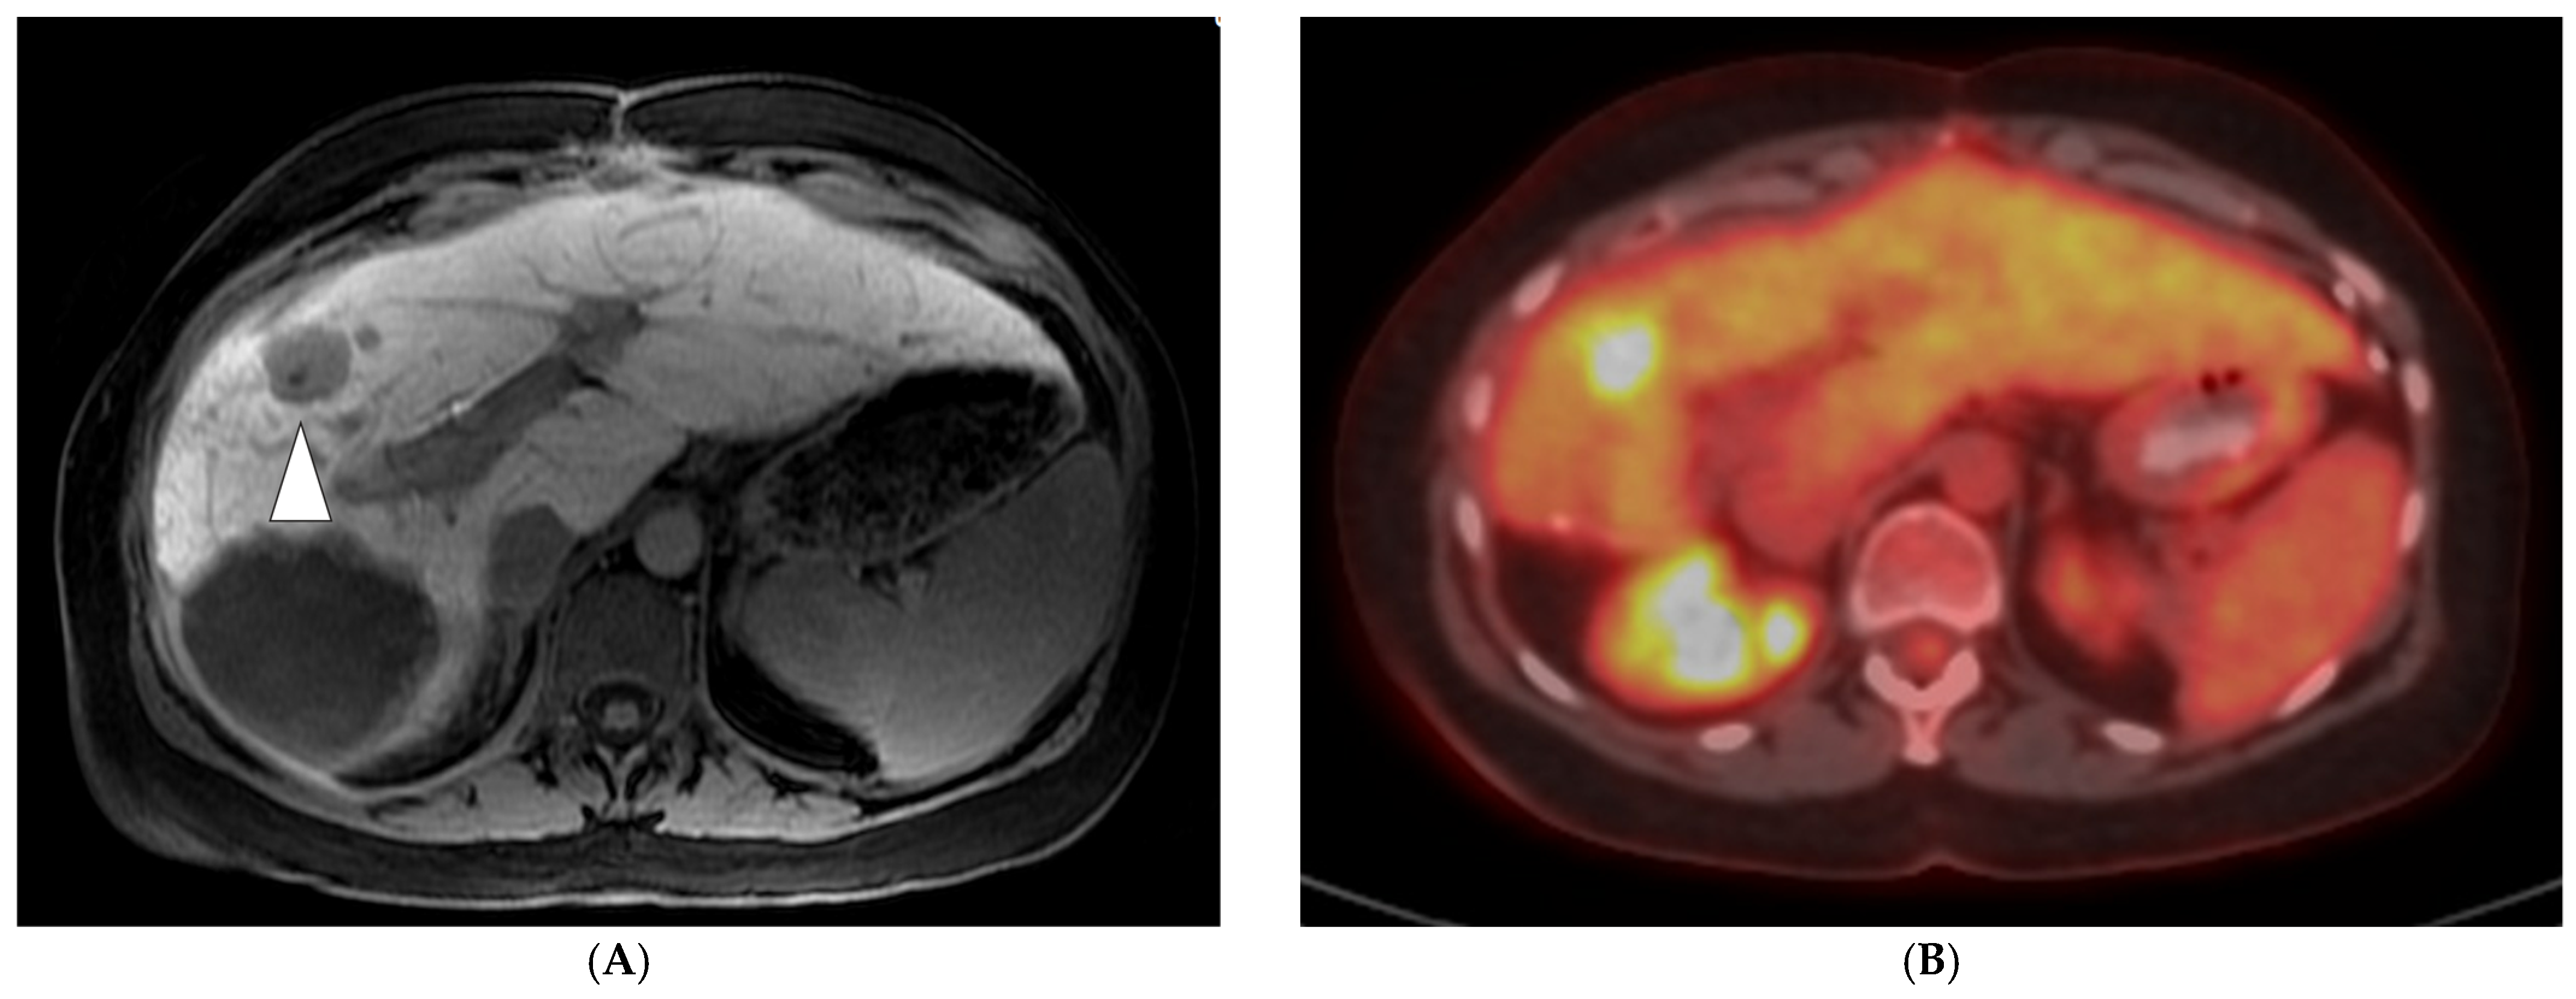

- Cornelis, F.H.; Petre, E.N.; Vakiani, E.; Klimstra, D.; Durack, J.C.; Gonen, M.; Osborne, J.; Solomon, S.B.; Sofocleous, C.T. Immediate Postablation 18F-FDG Injection and Corresponding SUV Are Surrogate Biomarkers of Local Tumor Progression after Thermal Ablation of Colorectal Carcinoma Liver Metastases. J. Nucl. Med. 2018, 59, 1360–1365. [Google Scholar] [CrossRef]

- Cornelis, F.; Storchios, V.; Violari, E.; Sofocleous, C.T.; Schoder, H.; Durack, J.C.; Siegelbaum, R.H.; Maybody, M.; Humm, J.; Solomon, S.B. 18F-FDG PET/CT Is an Immediate Imaging Biomarker of Treatment Success after Liver Metastasis Ablation. J. Nucl. Med. 2016, 57, 1052–1057. [Google Scholar] [CrossRef] [PubMed]

- Zirakchian Zadeh, M.; Yeh, R.; Kunin, H.S.; Kirov, A.S.; Petre, E.N.; Gönen, M.; Silk, M.; Cornelis, F.H.; Soares, K.C.; Ziv, E.; et al. Real-Time Split-Dose PET/CT-Guided Ablation Improves Colorectal Liver Metastasis Detection and Ablation Zone Margin Assessments without the Need for Repeated Contrast Injection. Cancers 2022, 14, 6253. [Google Scholar] [CrossRef]